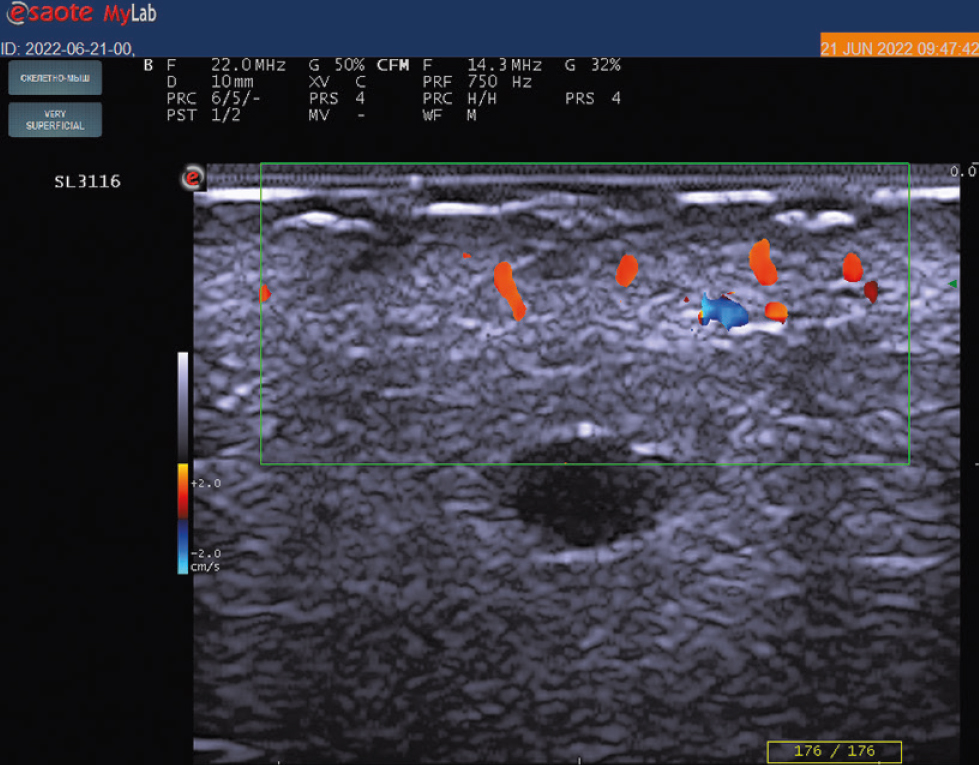

При оценке первичного энергетического допплерографического ультразвукового исследования кожи в области псориатических бляшек отмечены признаки повышения кровотока в сосочковом и сетчатом слоях кожи в виде множественных изолированных и сливных допплеровских сигналов по сравнению с отсутствием подобных сигналов в неповреждённой коже (рис. 2, 3). У большинства обследованных (47; 57,3%) наблюдались признаки II (умеренной) степени повышения кровотока, у 23 (28%) ― I (минимальной) степени, у 12 (14,6%) ― III (выраженной) степени. Среднее значение шкалы градации степени повышения допплеровского энергетического кровотока у пациентов при первичном исследовании составило 1,87.

Рис. 3. Ультрасонография с применением датчика 22 МГц (частота допплера 14,3 МГц, частота повторения импульсов 750 КГц): единичные дискретные допплеровские сигналы в дерме в области псориатической бляшки, соответствующие I степени повышения кровотока.

Fig. 3. Ultrasonography using a 22 MHz transducer (doppler frequency 14.3 MHz, pulse repetition rate 750 KGz of signals): Single discrete doppler signals in the dermis in area of psoriatic plaque, corresponding to the I degree of increased blood flow.